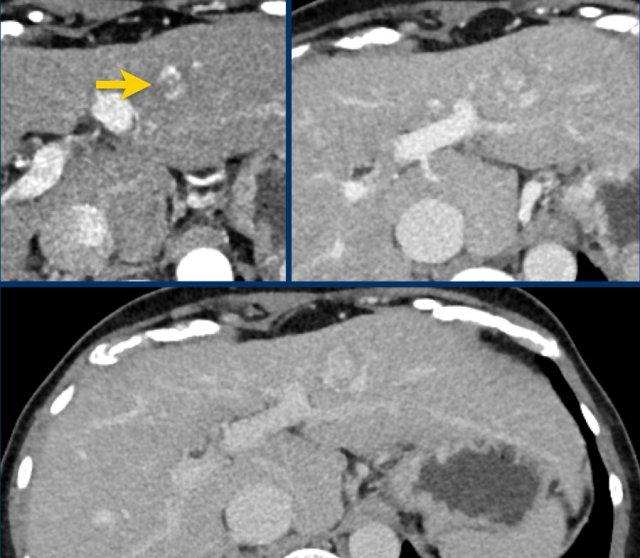

Arterial, PV and delayed phase images of a LIRADS 3 observation.

In segment 5 there is a subcapsular observation of intense arterial enhancement without washout in the PV or delayed phase.

Here a very small lesion which measures less than 10 mm with nonrim arterial hyperenhancement and one additional feature, i.e. LI-RADS 4.

The images show an arterially enhancing lesion with washout in segment VI. suspicious of HCC: LR-5.

Note that the arterial enhancement is faint because the patient is scanned in the early arterial phase instead of the late arterial phase in which HCC has it’s peak enhancement.

Additional small lesions can therefore be easily missed.